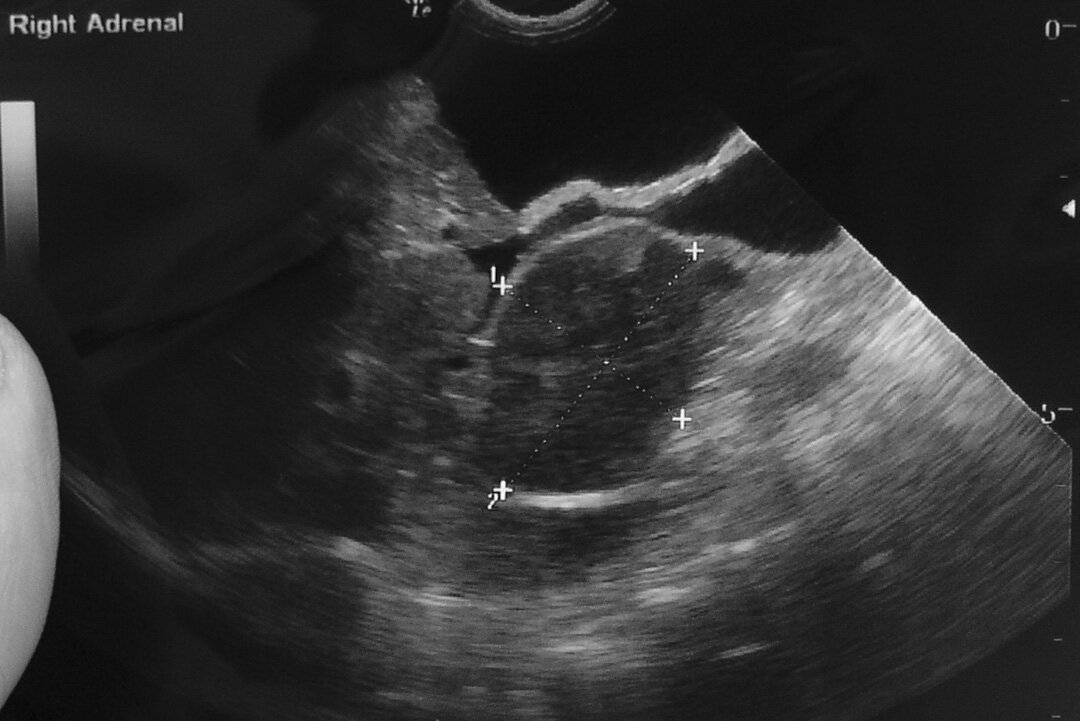

УЗИ правого надпочечника у собаки

Средний размер надпочечников у собак: длина 0.8-3.3см, ширина 0.6-1.8см, толщина 0.2-0.8см. Средний размер надпочечников у кошек: длина 0.8-1.5см, ширина 0.5-1.0см, толщина 0.2-0.4см.